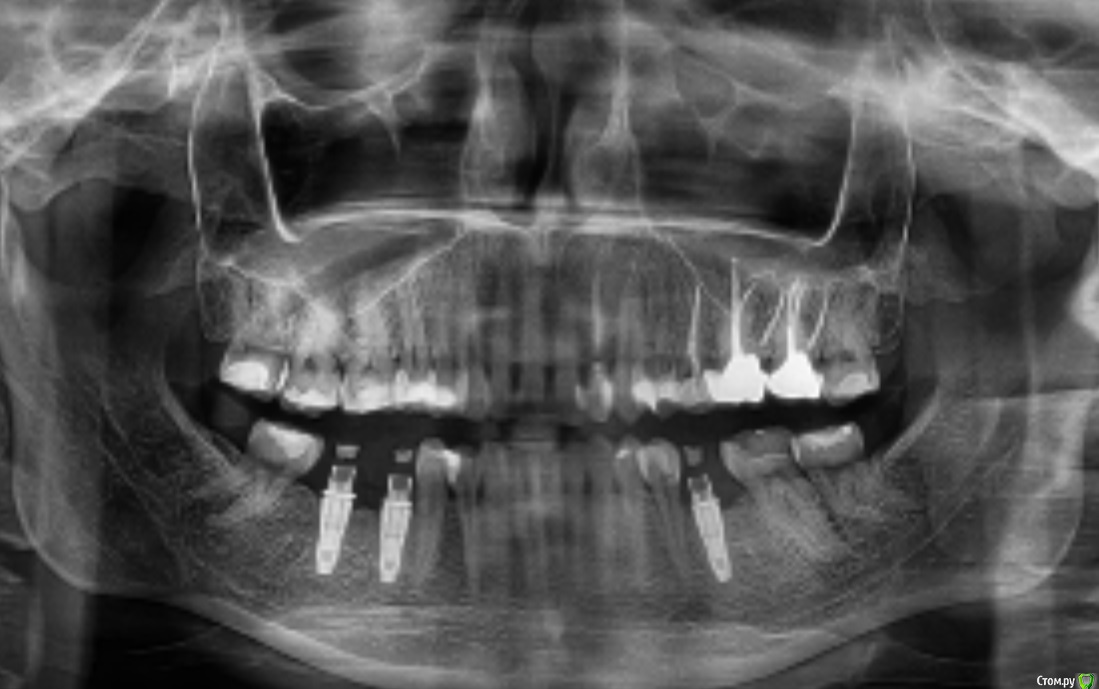

Pavel-Pskov Опубликовано 25 февраля, 2019 Поделиться Опубликовано 25 февраля, 2019 Скорее всего контакты неплотные между времянками и зубами, с имплантами по этому снимку проблем не видно. Ссылка на комментарий

колесников Опубликовано 3 марта, 2019 Поделиться Опубликовано 3 марта, 2019 (изменено) Есть вопросы к позиционированию имплантов и объёму десны возле их платформ. Необходимо фото во рту с коронками в боковой проекции и без них,но сверху Изменено 3 марта, 2019 пользователем колесников Ссылка на комментарий